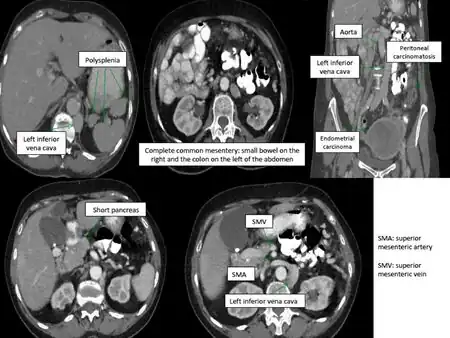

Situs ambiguous (with polysplenia and left IVC)- Abdominal anatomic anomalies detected in CT- scan

For proper diagnosis of situs ambiguus, cardiac and non-cardiac features must be evaluated. Diagnostic criteria for atrial isomerism includes observation of symmetry of thoracic visceral organs upon echocardiogram, arrhythmia upon electrocardiogram, and chest x-ray for confirmation of the heart's location across the left-right axis. Additional radiographic and cross-sectional imaging may be obtained to evaluate both cardiac and non-cardiac manifestations of situs ambiguus. In addition, a series of gastrointestinal tests can be conducted for observation of intestinal malrotation, as well as a scan of the liver and spleen for biliary function.[2]